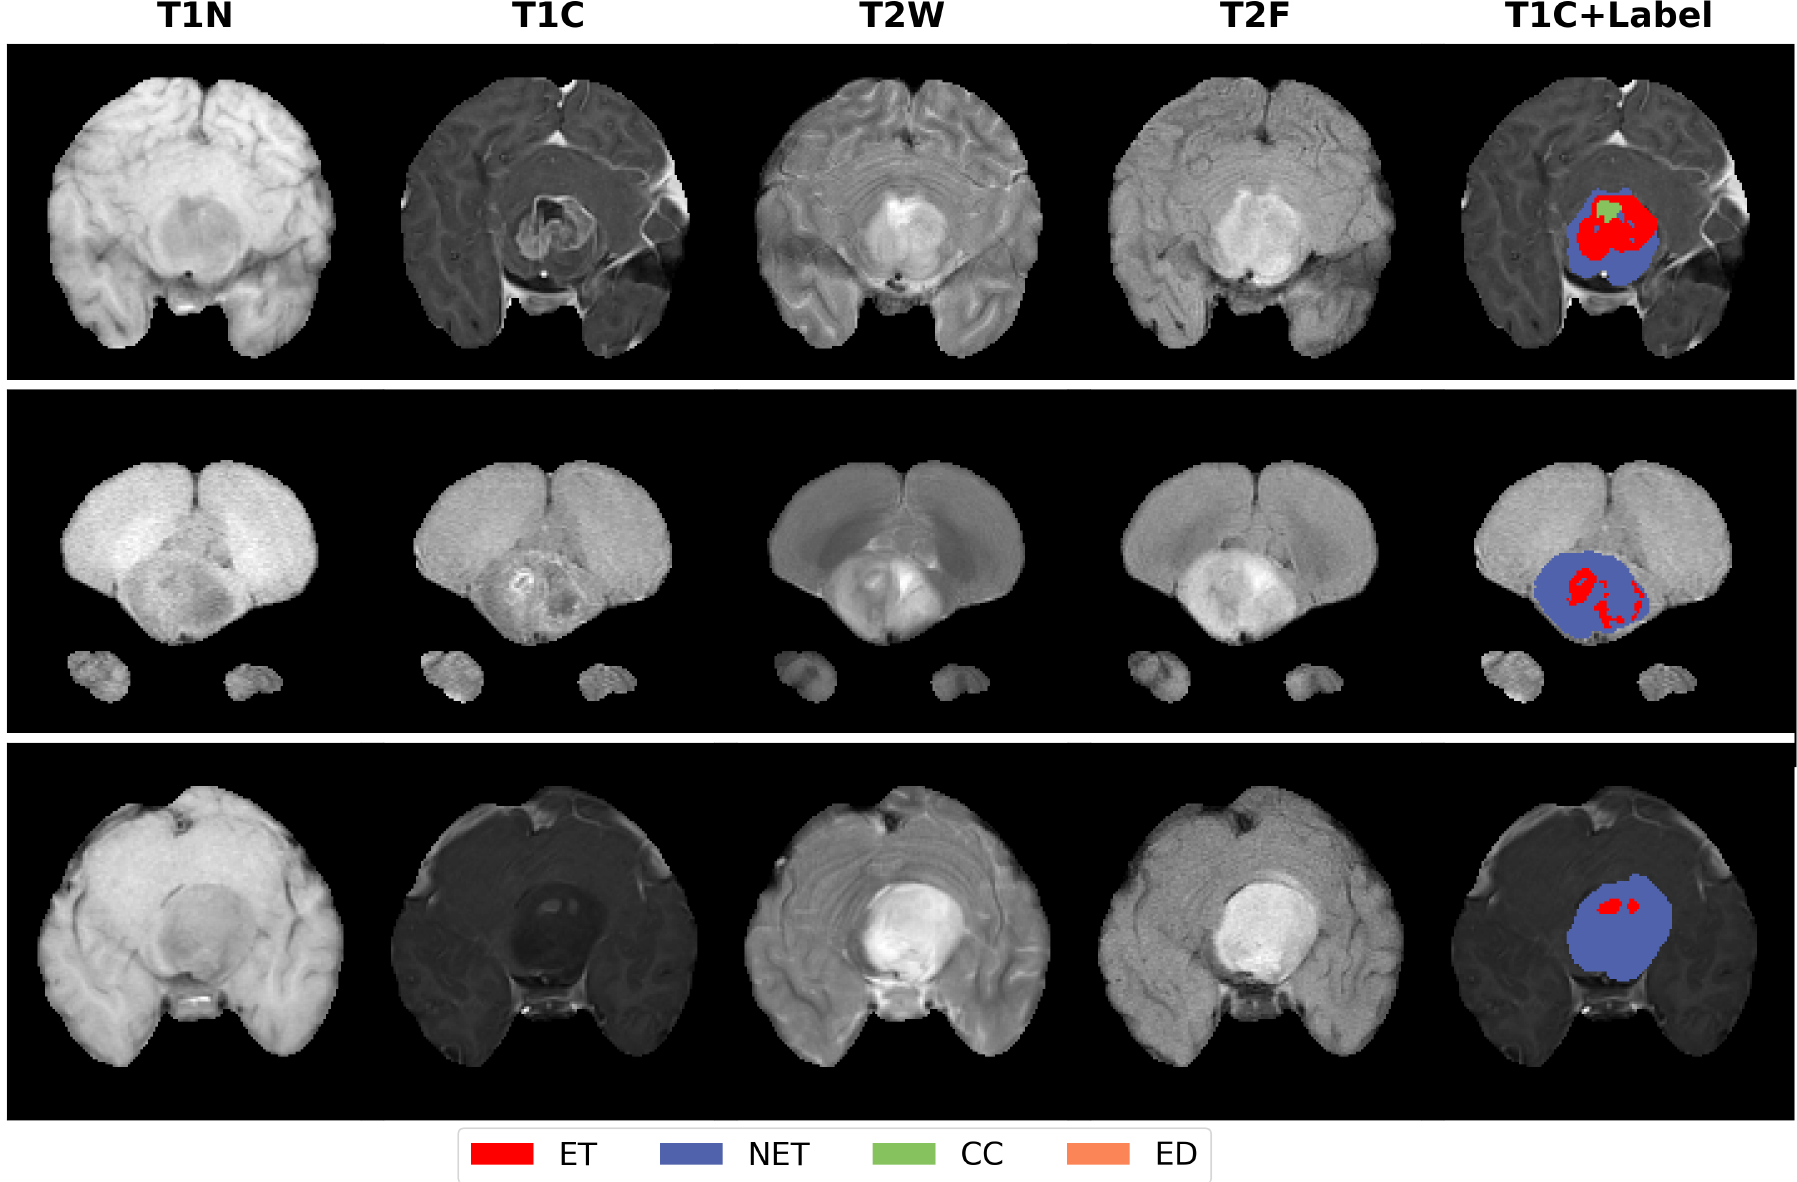

3.2 Qualitative Results

Fig. 3 presents the qualitative segmentation results of the final ensemble model on validation data. The validation set underwent the same skull stripping and frequency domain decomposition preprocessing.

Refer to caption

Figure 3: Quantitative results of the final model on the validation set. The three selected examples correspond to BraTS-PED-00310-000, BraTS-PED-00315-000, and BraTS-PED-00318-000, respectively.